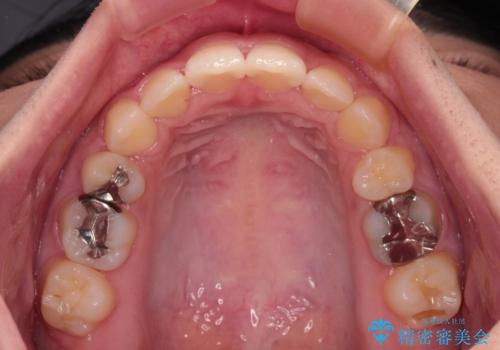

- 口元の突出感を気にして来院された患者様です。

デコボコと口元の突出感が認められたため、上下左右の第1小臼歯4本を抜歯してのワイヤー矯正を行うこととしました。

上顎歯列の横幅が狭く、下顎大臼歯の歯軸が舌側に倒れていたため、急速拡大装置により上顎骨を側方に拡大し、咬み合わせを改善することとしました。

上顎歯列幅を拡大したことで、デコボコを容易に解消することができるようになったため、抜歯により得られたスペースを口元の突出感改善に利用することができました。